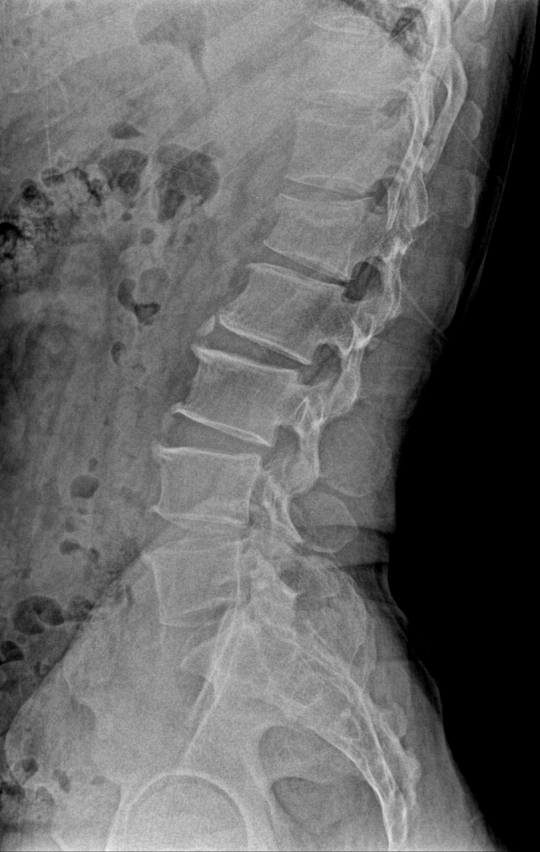

척추압박골절 X-RAY / 바른세상병원 척추센터 제공

척추압박골절은 외부 충격에 의해 척추뼈가 납작하게 내려 앉는 질환으로 골다공증이 주 원인이다. 하지만 골절이 발생하기 전까지 골다공증 진행여부를 알 수 없는 경우가 많기 때문에 골밀도가 낮은 어르신들이나 폐경기 이후의 여성들은 가을 산행을 할 때 사소한 충돌이나 넘어짐에도 각별히 주의해야 한다.

척추압박골절이 발생하면 누워있거나 앉아 있다가 자리에서 일어나려고 할 때 통증을 느낀다. 압박 골절이 악화되면 등과 허리가 굽게 되는 척추후만증이 발생할 수도 있기 때문에 이상을 느끼면 무리하게 움직이지 말고 안정을 취하는 것이 좋고, 전문의를 찾아가 치료를 받아야 한다.